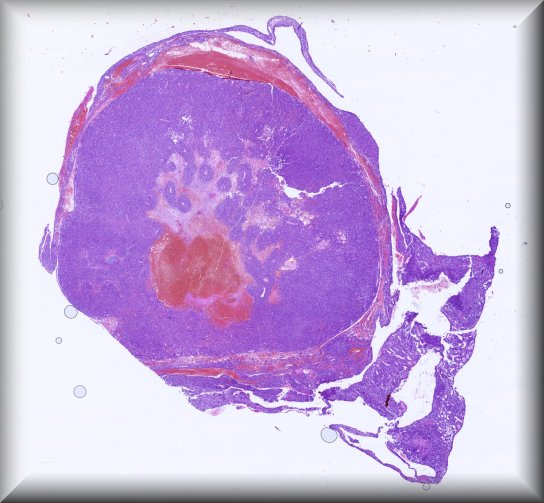

Rita Van Ginderdeuren (Leuven): Vitreous sample in chronic posterior uveitis, unresponsive to steroid treatment |